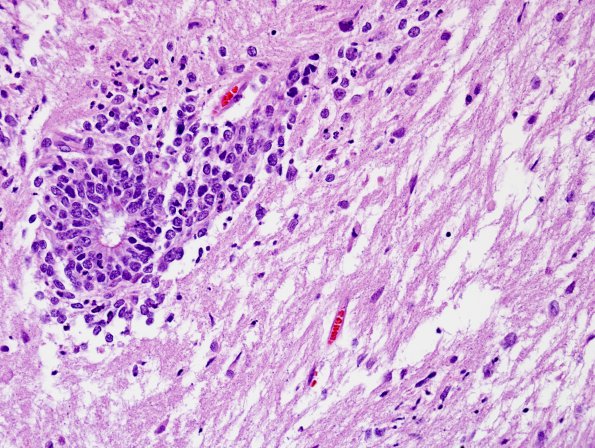

Some of these cells are arranged in the form of true rosettes. The rosettes contain variably sized central lumina and are multi-layered with highly proliferative cells. (H&E)